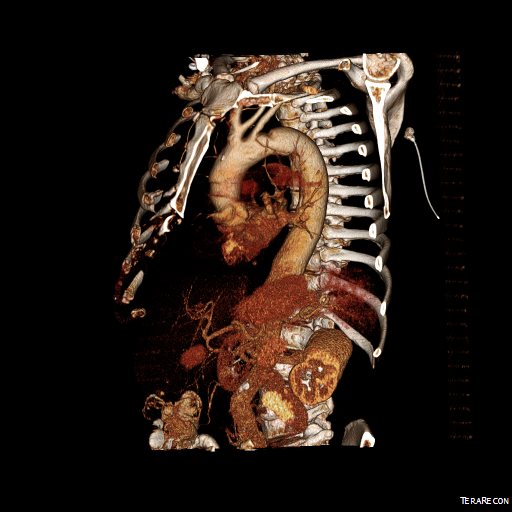

The figure above shows the summarizes the problem that brought the patient to his local hospital and triggered his transfer to our acute aortic syndrome unit. The concept is that all chest pain of cardiovascular origin gets intake through a vast intensive care unit staffed by cardiovascular intensivists. Stabilization, workup, transfer to operating room or interventional suite all happens in an ICU that encompasses almost a city block.

The patient is an older middle aged man with sudden onset of back and abdominal pain. He was on coumadin for a prior SMV thrombosis and treatment for a ruptured appendicitis -antibiotics with plan for staged appendectomy. CT at his local hospital revealed a type B aortic dissection (TBAD) that extended into his superior mesenteric artery.

The dissection started at the left subclavian artery origin. The false lumen compressed the true lumen up at the proximal descending thoracic aorta. This is an important finding because in this configuration with much of the filling of the dissection from the distal reentry sites, the false lumen acts like a pressurized, compressive lesion. With time, the adventitia around the false lumen may become aneurysmal if the false lumen fails to thrombose or obliterate. When the dissection is acute, the flap may cause a direct obstruction to flow or a dynamic one that depends on the pressure difference between true and false lumen.